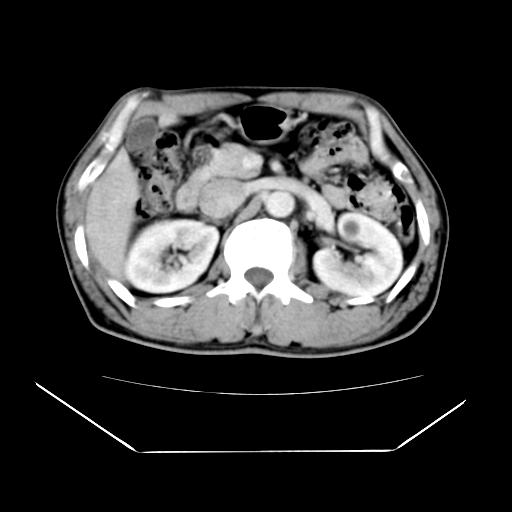

男性,55岁,外院体检afp明显升高,但b超未发现异常,否认乙肝病史。来我院ct增强。有延时扫描。

左肾囊肿.右肺中叶内侧段钙化灶.慢性胆囊炎.

肝脏右叶动脉期可见低密度影,至延迟期被充填,考虑血管瘤可能性大。

肝右叶病灶

不排除肝右叶肝癌可能。

这个不是肝右静脉吗,这么大的病灶b超不可能发现不了吧

如果这个是癌灶的话则下腔静脉有瘤栓可能

肝6段血管瘤

血管瘤可能性大。

是肝右静脉吧

考虑肝右静脉影。